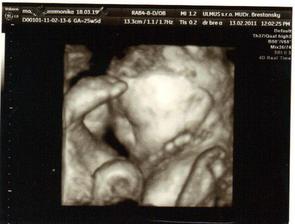

✿♥♥♥♥Bude to dievčatko!!!!! ♥♥♥♥✿

Bude to Stella 🙂

krasne 3D sono 🙂

Krasne foto dufam ze ti uz je lepsie mojko 🙂